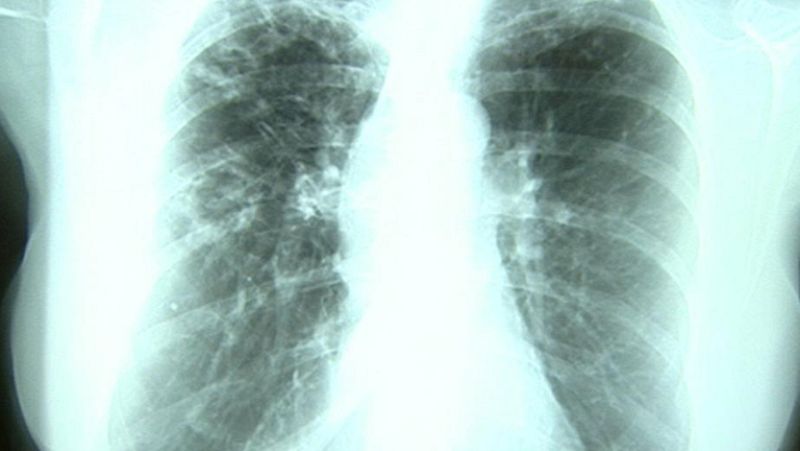

Un paciente que padece tuberculosis sopla aire como parte del tratamiento médico

La pandemia de COVID-19 ha revertido años de progreso mundial en la lucha contra la tuberculosis (TB) y, por primera vez en más de una década, las muertes por esta enfermedad infecciosa, según el informe mundial sobre la tuberculosis 2021 de la Organización Mundial de la Salud (OMS).

Aproximadamente 1,5 millones de personas murieron por la tuberculosis en 2020 (incluyendo 214.000 entre los seropositivos) y este aumento se produjo principalmente en los 30 países con mayor carga de TB. Además, las proyecciones de la OMS sugieren que estas cifras podrían ser mucho mayor en 2021 y 2022.